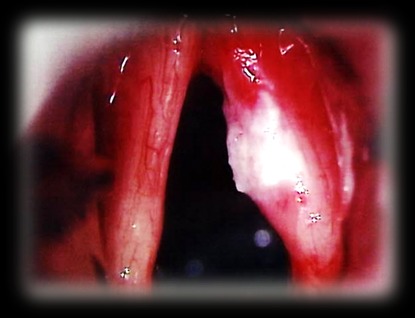

Плоскоклеточный высокодифференцированный рак